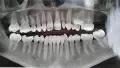

У меня растёт клык поверх зубов, т.к. ему не хватает места. Из-за него у меня неправильный прикус и вообще не очень красивая улыбка. В интернете пишут, что в 16 лет уже поздно делать что-то, т.к. клык может уже не встать не место.

Можно ли что-то сделать? Как можно выровнять зубы?

После осмотра, рентген диагностики, оценки прикуса и моделей челюстей, скорее всего Вам предложат удалить некоторые зубы (чаще это премоляры), чтобы на их место встал клык. И установят брекеты (есть металлические и сапфировые - очень эстетичные).